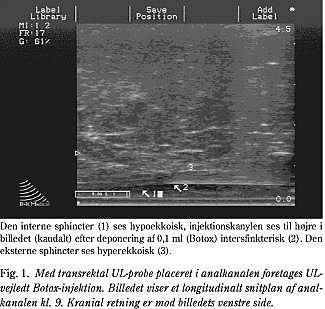

Hos de patienter, der blev behandlet med botulinum-toksin (Botox), blev dette under fuld anæstesi injiceret under vejledning af en biplan TRUS-scanner (Fig. 1). I alt 20 enheder blev placeret intersfinkterisk i fire depoter og/eller ved underkanten af m. puborectalis. Stoffet blev injiceret i det intersfinkteriske rum, fordi dette er UL-mæssigt veldefineret, samtidig med at placering her vil tillade binding både til den interne og eksterne sphincter. Syv af de ni patienter som fik injektion af botulinum-toksin accepterede, at der blev taget en UL-vejledt biopsi af analsphincter.